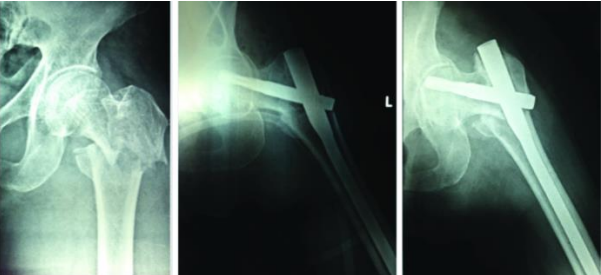

Table/Figure 3: - A 31.A3 fracture treated with PFN, with good union at one year follow up.